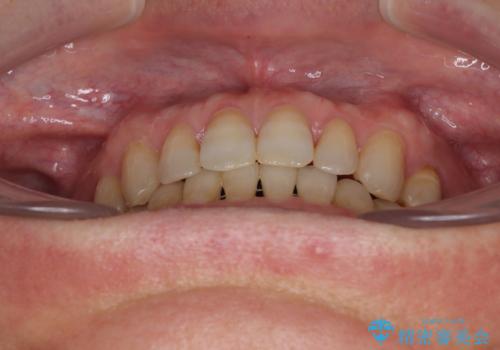

- 前歯のデコボコと隙間の空いた歯列を気にして来院された患者様です。

下顎前歯が隠れるほどのディープバイトにより、強い咬合力と突き上げで上顎歯列に隙間が空いている状態でした。

ディープバイトが改善され、睡眠時の食いしばりも緩和され、顎への負担が軽減されました。